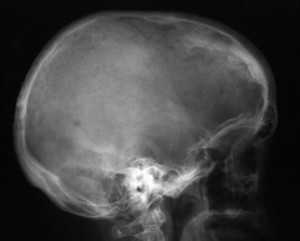

Диагноз ставят на основе жалоб и клинической картины; также используют гистологические методы исследования. На рентгенограмме визуализируется утолщение лобной кости. Синдром Морганьи — Стюарта — Мореля дифференцируют в первую очередь от болезни Иценко — Кушинга и адипозогенитальной дистрофии.

Основным проявлением синдрома М.С.М., без которого он не существует как таковой, является утолщение внутренней пластинки лобной кости (гиперостоз). Это своеобразное разрастание гиперплазированной костной ткани, хорошо распознаваемое рентгенологически и не определяемое при осмотре и пальпации. Явление это довольно распространенное, но в большинстве случаев не проявляется клинически и является рентгенологической находкой [18, 34, 35].

Рентгенологически определяются костные разрастания на поверхности внутренней пластинки лобной кости; они могут быть довольно ограниченными или занимать обширные участки. Иногда они диффузно распространяются на свод черепа, реже - на его основание.

Рентгенограмма черепа (боковая проекция) больного с синдромом Морганьи: резкое утолщение лобной кости (указано стрелкой) за счет гиперостоза внутренней пластинки.

Диагноз устанавливают на основании клин, картины и данных ЭЭГ. Для уточнения диагноза необходимо рентгенол, исследование, т. к. гиперостоз внутренней пластинки лобной кости (рис.), являющийся обязательным признаком этого синдрома, может быть выявлен только при краниографии (см.). О локализации и протяженности изменений судят по снимкам черепа в боковой проекции. Как правило, дополнительные костные разрастания в виде отдельных узлов или разлитого характера располагаются в средней и нижней третях чешуи лобной кости, изредка — и в теменных костях. По сравнению с неизмененными участками кость может быть утолщена в 2—3 раза. Этим изменениям могут сопутствовать различной формы и размеров очаги обызвествления твердой мозговой оболочки в зоне, примыкающей к внутренней поверхности лобной кости.

При длительном течении заболевания и резко выраженном гиперостозе лобной кости из-за уменьшения объема черепа на краниограммах могут быть обнаружены признаки повышения внутричерепного давления (усиление пальцевых вдавлений, углубление борозд синусов и др.).